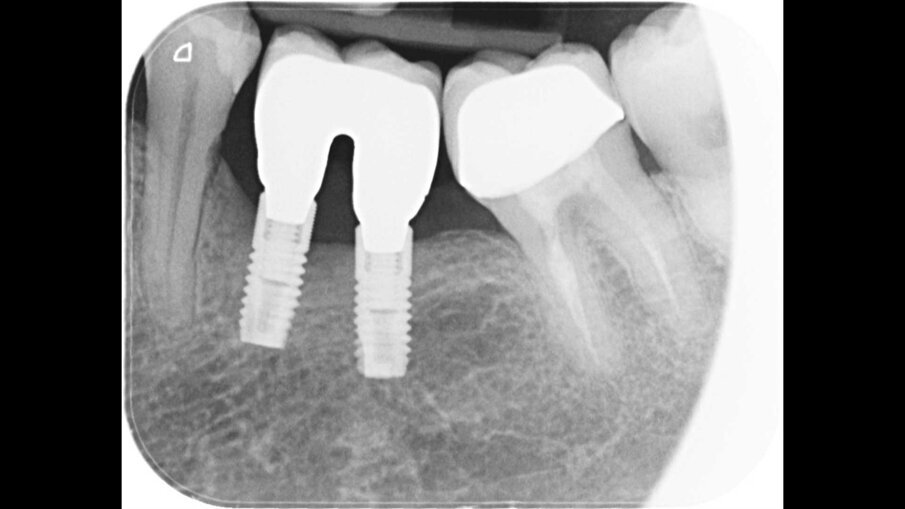

Un paziente di 47 anni, non fumatore e in buono stato di salute, all’esame clinico presenta una perimplantite diagnosticata dopo 7 anni di carico a livello degli impianti 3.5 e 3.6, con un sondaggio di 8 mm sull’aspetto mesiale dell’impianto 3.5 e di 4,5 mm sull’aspetto distale del 3.6. La radiografia conferma la perdita ossea attorno all’impianto distale e ancora più evidente a livello dell’impianto mesiale (Fig. 1). Si decide di trattare il caso chirurgicamente decontaminando la zona affetta, utilizzando il gel REGENFAST per potenziare il trofismo topico e inserendo la matrice Geistlich Fibro-Gide a sostegno dei tessuti molli coronali. Si procede con il trattamento chirurgico, esponendo il difetto per rimuovere il tessuto di granulazione (Fig. 2). La superficie implantare esposta è ulteriormente ripulita con ultrasuoni, spazzolino in titanio, passando all’interno delle spire e risciacquando con soluzione fisiologica e garze sterili (Fig. 3). Successivamente, il gel REGENFAST è dosato e posizionato direttamente all’interno del difetto perimplantare mediante spatolina o puntale (Fig. 4). La matrice Geistlich Fibro-Gide è ritagliata in modalità “Collagen-Ring” affinché possa essere posizionata attorno al collare implantare, sostenendo i tessuti molli che non collasseranno all’interno del difetto (Fig. 5). La matrice, grazie all’elevata porosità è completamente permeata di sangue permettendo la stabilizzazione del coagulo. La matrice viene ulteriormente imbevuta di gel REGENFAST così da potenziare i fisiologici processi rigenerativi (Fig. 6).

Fig. 1 - Radiografia iniziale che evidenzia la perimplantite in zona 3.5 e 3.6.